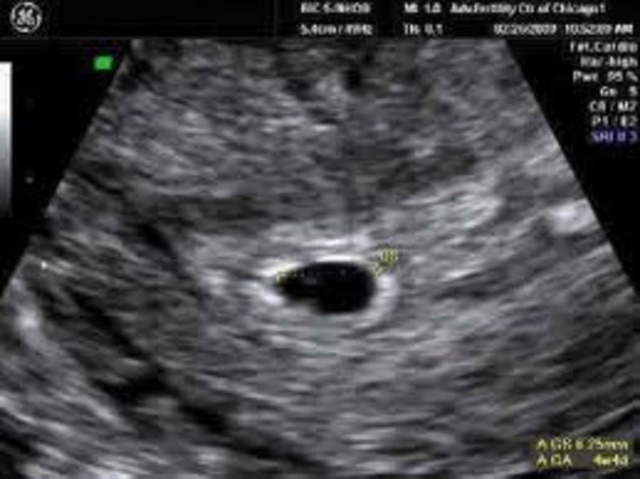

At two weeks the baby is the size of a pin head.

The egg has hatched into the lining of the uterous. This is the critical stage for spinal cord and brain development. The internal organs and circulatory system begin to form. The heart starts to beat.